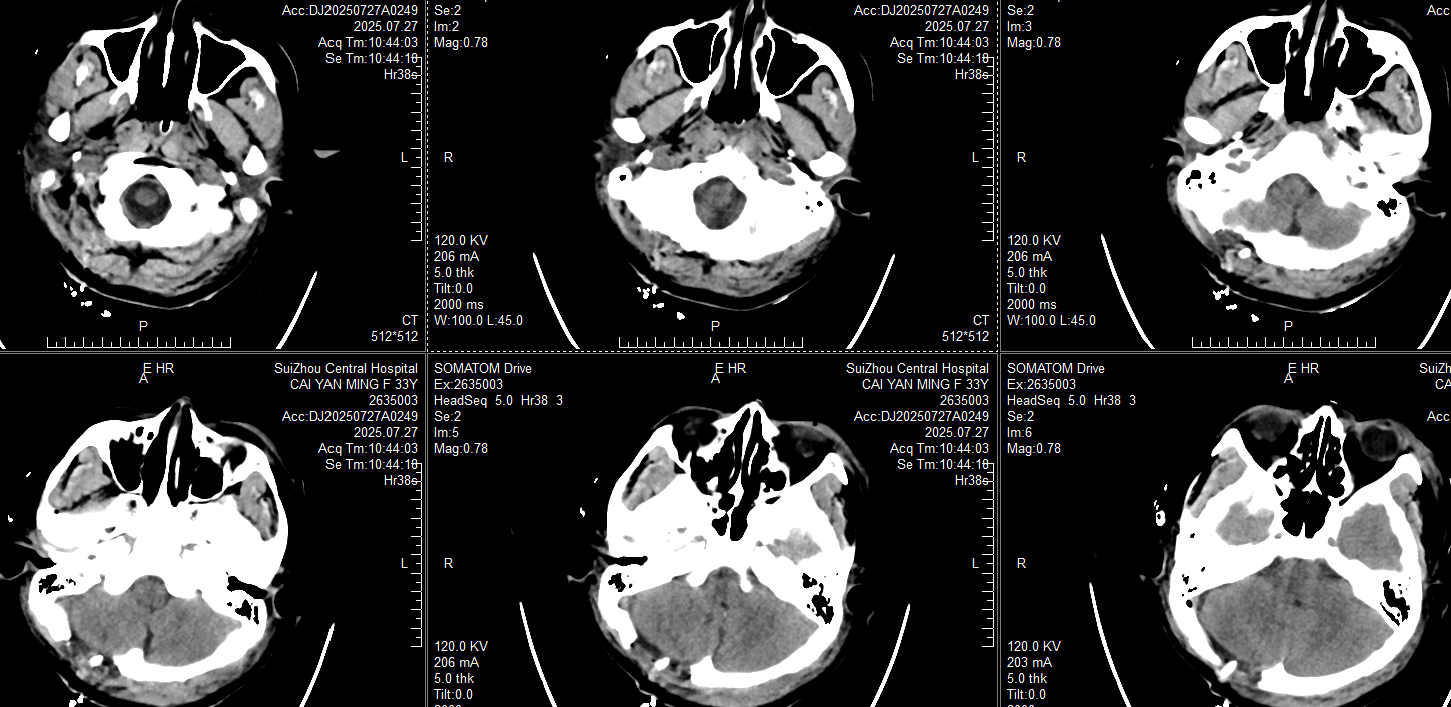

18:56急诊科CT: